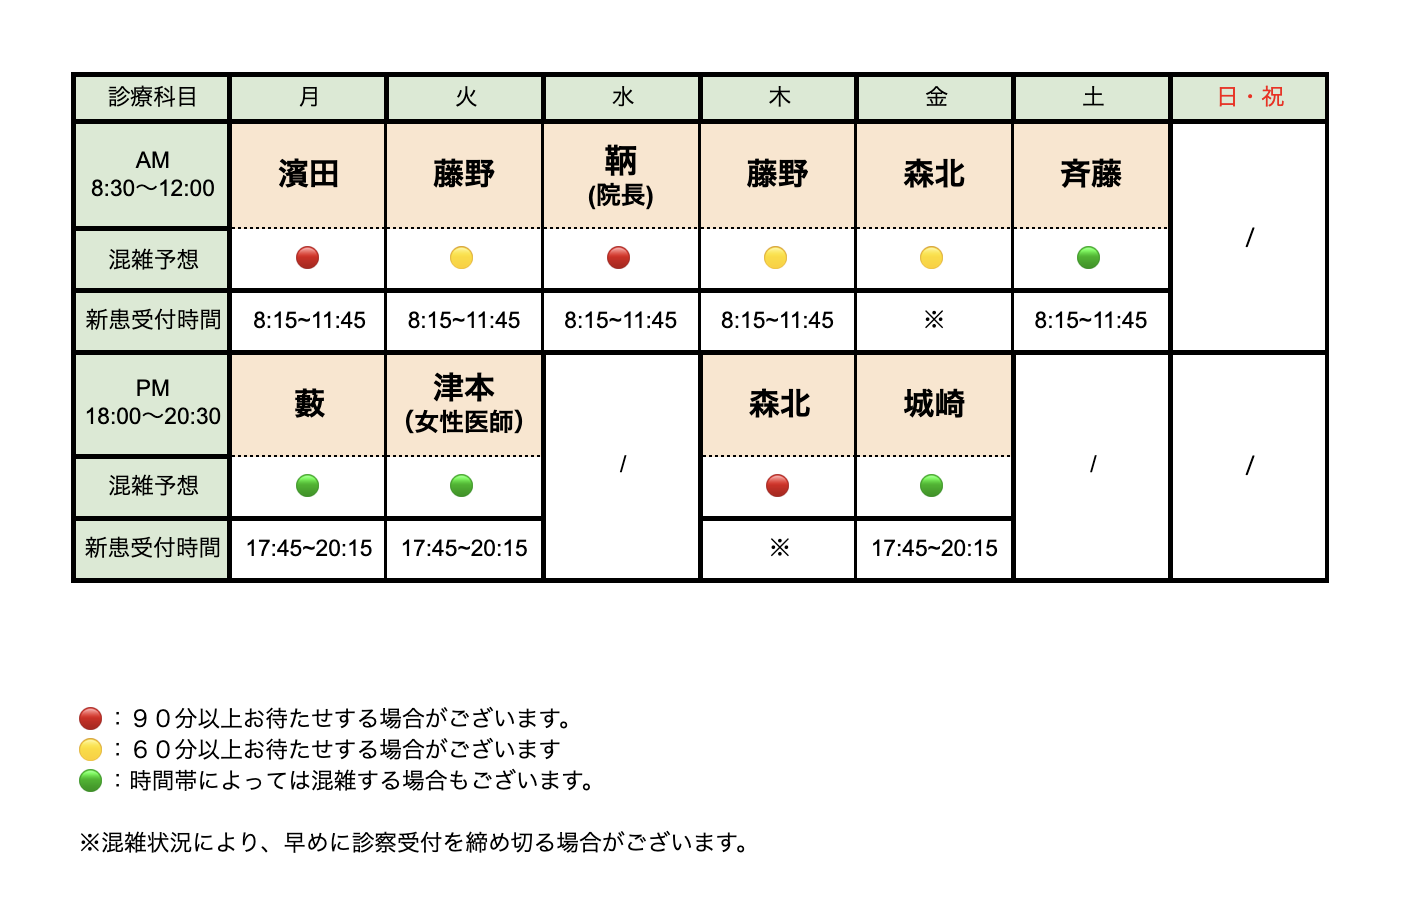

骨粗鬆症の診断は、レントゲン検査で行っております。

骨粗鬆症の治療は、内服薬や注射による治療を行います。